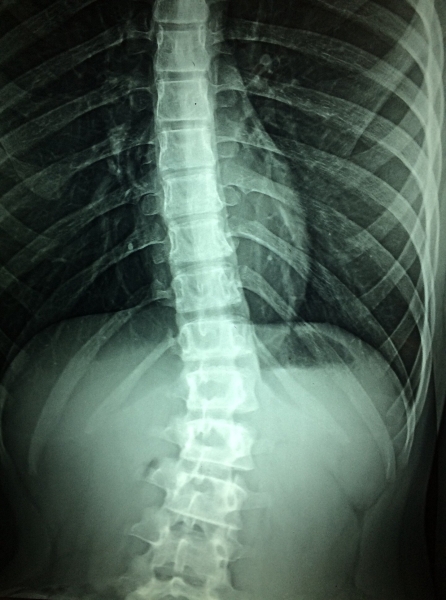

研究中,脊髓靶向的硬膜外电刺激(epidural electrical stimulation,EES)用于产生稳定血流动力(稳定全身的血流),保证重要器官维持合适的血供。研究人员发现,精确放置的脊髓刺激器与交感神经系统回路共同控制了血压。新的发现促进拟神经闭环交流系统(neuroprosthetic closed-loop communication system)的开发,可用于恢复血流动力学调控。